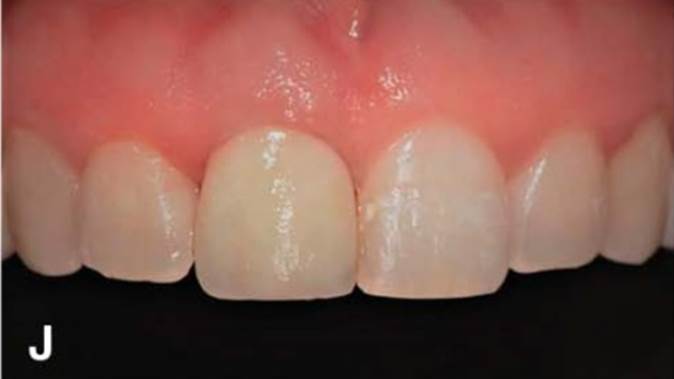

Clinical case: Immediate post-extraction insertion of implant & immediate loading

- Courtesy of Prof. Giuseppe Luongo, Italy -

AnyRidge, immediate loading, single implant, multicenter study, maxillary anterior, Prof. Giuseppe Luongo, single replacement

AnyRidge implant system

Immediate functional loading of single implants: a multicenter study with 4 years of follow-up

/J Dent Res Dent Clin Dent Prospect 2018; 12(1):26-37 | doi: 10.15171/joddd.2018.005

https://www.ncbi.nlm.nih.gov/pubmed/29732018